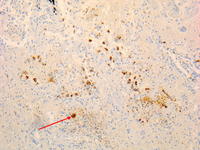

Coxiella burnetii chronic hepatitis of a patient with endocarditis: immunohiostochemistry. Note the absence of doughnut granuloma seen in acute Q fever. Brown coloration identifies bacteria in monocytes/macrophages

Hubert Lepidi, Institut Hospitalo-Universitaire Méditerranée Infection